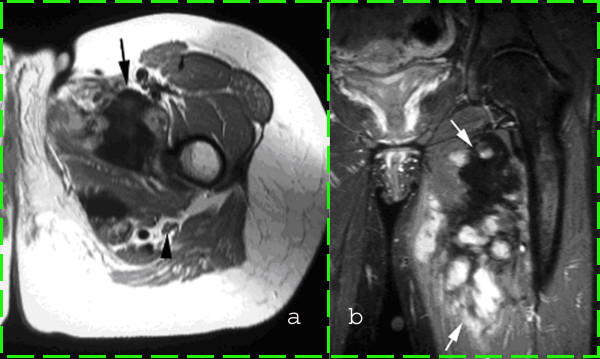

The work described in this paper is motivated by the realization that articles in scientific publications contain a substantial amount of figures consisting of two or more subfigures, which could be treated as separate images for the purpose of automatic content-based analysis or indexing for retrieval. Figure 1 shows two examples of such compound figures found in a dataset of article images of the biomedical literature. Based on published datasets drawn from open access biomedical literature, it has been estimated that between 40% and 60% of figures occurring in articles are compound figures Apostolova2013 ; Chhatkuli2013 ; Herrera2013 .

For CFC, we propose several global image features designed to capture the existence of edges or whitespace that could potentially separate subfigures and use them with well-known supervised machine learning algorithms. For CFS, we designed an image processing algorithm comprising distinct modules for detecting two types of separators between subfigures: (1) homogeneous rectangular areas of whitespace spanning the entire image width or height, which we call separator bands (shown in Fig. 1(a)); and (2) separator edges spanning the entire image width or height, which may arise from borders drawn around subfigures or from adjacent subfigures “stitched together” as shown in Fig. 1(b). The proposed CFS algorithm internally uses a separate binary classifier (independent from CFC) to decide which of the two separator detection modules to apply to a given compound image. Based on the observation that compound images containing graphical illustrations (such as diagrams and charts) often contain separator bands, whereas most subfigures in other compound images show rectangular border edges, we train the internal CFS classifier to discriminate between graphical illustrations and other article images and call it illustration classifier.